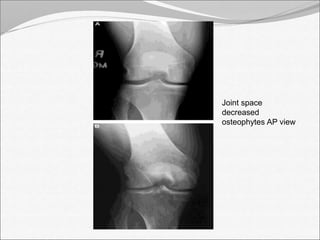

Joint space

decreased

osteophytes AP view

Joint space decreased osteophytes AP view